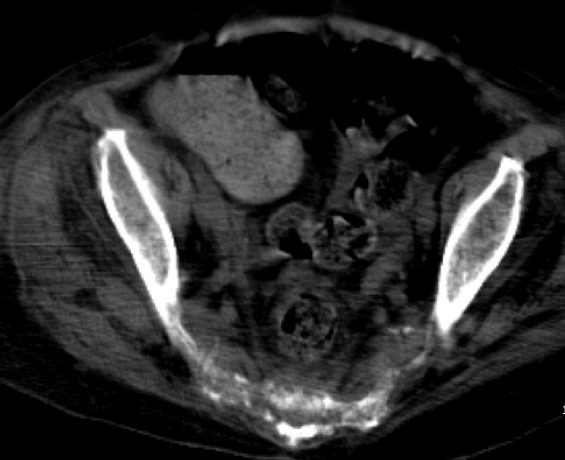

Figura 2. TC senza mezzo di contrasto che mostra l’infiltrazione del sacro

Si rendeva pertanto necessario proseguire l’iter diagnostico presso ambiente specialistico internistico-ematologico. Le Figure 1-4 mostrano le immagini della regione sacrale e del mesoretto ottenute mediante RM e TC.